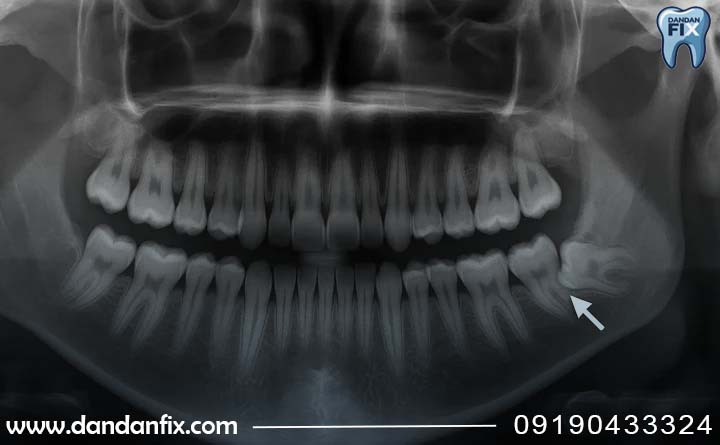

مرحله بعدی و مهمترین بخش تشخیص، عکس برداری از دندانها است. معمولا یک عکس رادیولوژی ساده به نام عکس پانورامیک گرفته میشود. این عکس به دندانپزشک نشان میدهد دندان عقل دقیقا کجا قرار دارد، به چه سمتی رشد کرده و آیا به دندان کناری یا استخوان فک فشار میآورد یا نه. بدون این عکس، تشخیص دقیق نهفتگی امکان پذیر نیست.

در بعضی افراد، دندان عقل داخل استخوان فک پنهان است و هیچ علامت ظاهری ندارد. در این حالت، فقط با عکس برداری میتوان متوجه نهفتگی شد. به همین دلیل، حتی اگر درد شدیدی نداشته باشید، بررسی دورهای دندانها کمک میکند دندان عقل نهفته زودتر تشخیص داده شود و از مشکلات بعدی جلوگیری شود.

بهطور خلاصه، معاینه ساده دندانپزشک همراه با عکسبرداری بهترین و مطمئنترین راه برای تشخیص نهفتگی دندان عقل است.